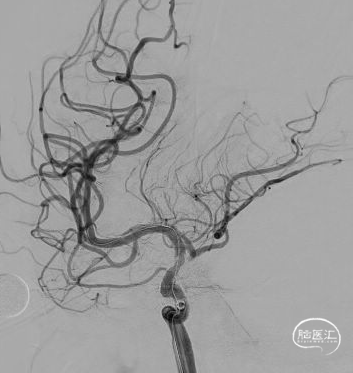

前交通开放代偿右侧大脑中动脉。

后循环未向右侧大脑中动脉代偿供血。

病变展示:右侧颈内动脉后交通段次全闭塞。

2.0×9mm球囊扩张,可见残余狭窄较重。

二次球囊扩张后可见狭窄明显改善,血流速度增快。

植入3.5×15自膨支架。

工作角度造影示:支架完全打开,贴壁良好。

术后正侧位及工作角度造影:支架贴壁良好,血流通畅。